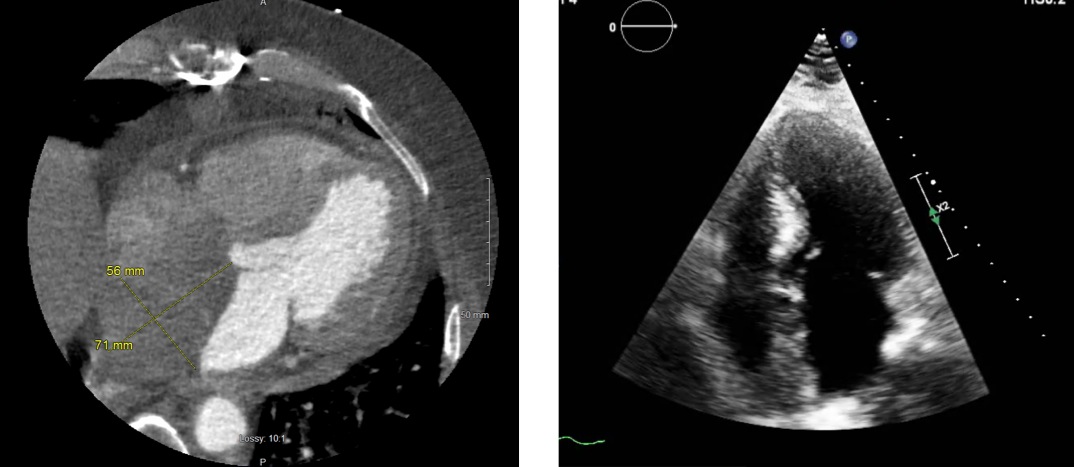

Case Presentation: The patient is a 64-year-old male, BMI 35.6 kg/m2, with a history of diabetes mellitus II, hypertension, hyperlipidemia, and recent CAD after syncope, who was under going CABG. A cardiac tumor was incidentally found intraoperatively (Figure 1). The pre-operative transthoracic echocardiogram (TTE) was negative for signs of tumor (Figure 2), however, when it was visualized during surgery an intraoperative transesophageal echocardiography (TEE) confirmed the mass. Postoperative cardiac CTA (Figure 3) depicted a large, non-enhancing mass measuring 8 x 5.5 cm. This mass filled the entire right atrium, producing mass effect on the left atrium, extending into the superior aspect of the right ventricle and potentially infiltrating the IVC. Cardiac biopsies obtained intraoperatively revealed cells with marked nuclear pleomorphism and increased mitotic figures. They stained positive for pan keratin, vimentin, Factor VIII, CD31, and CD34, consistent with a diagnosis of high-grade angiosarcoma. A repeat TTE after diagnosis of the tumor again failed to identify the mass. While awaiting palliative chemotherapy, the patient had numerous readmissions over the next two months for recurrent shortness of breath due to fluid overload. He eventually passed away within 2 months of the initial diagnosis.

Discussion: TTEs, with 75% sensitivity, are commonly perceived as the initial diagnostic tool for cardiac malignancies. As demonstrated in this case, repeated TTEs all failed to identify our patient’s large intracardiac mass, which raised concern regarding its validity on obese patients. TEEs, despite having 97% sensitivity and identifying the cardiac angiosarcoma, are not generally used in an effort to pursue more cost-effective medicine and avoid an invasive procedure.